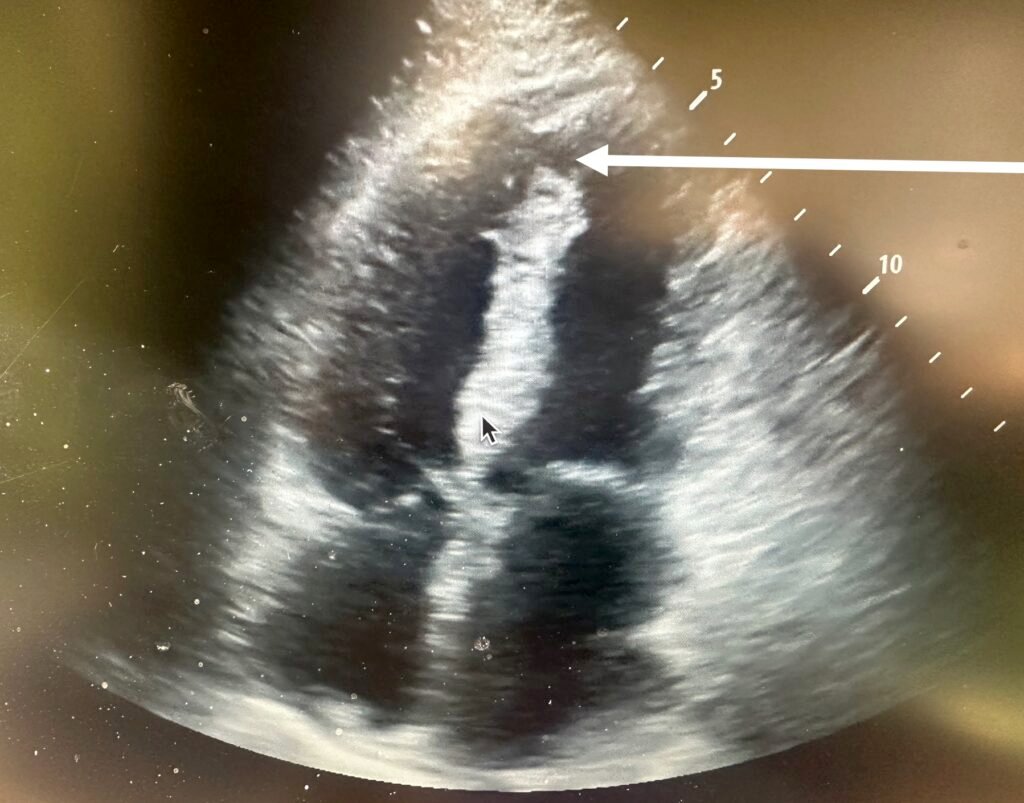

Here is a still image which shows the finding. Do you see it?

Here I point it out with an arrow:

There is a large ventricular septal rupture. I could hardly believe my eyes because the patient was comfortable without dyspnea or chest pain, and after fluids had a normal blood pressure.

I consulted cardiology a formal echo was done:

–Apical ventricular septal defect, left to right shunt.